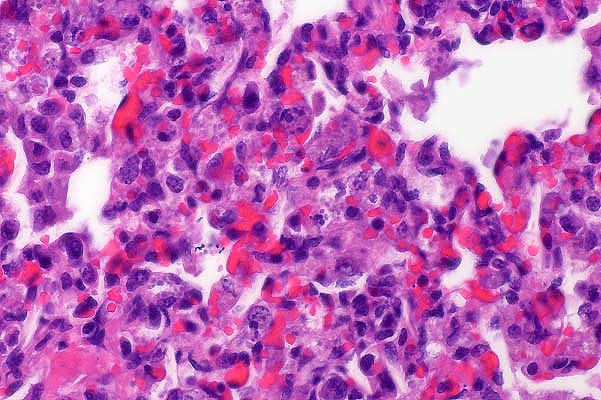

- 1. Colon: subacute multifocal moderate to severe granulomatous

colitis with sections of nematode larvae in the lamina propria

mucosa and tela submucosa.

2. Moderate submucosal edema.

Etiology: Larval cyathostomiasis

- According to the stage of inflammation, focal or diffuse

mucosal infiltrations with macrophages and neutrophils or parasitic

granulomas dominate the lesions. The amount of eosinophils varied

within the affected areas. In the submitted slides no eosinophils

could be detected. The mucosal nodules consisted of larvae residing

in dilated glandular crypts of mucosal cysts. The submucosal

nodules contained parasites with a fibrous capsule surrounded

by an intense inflammatory reaction, composed largely of macrophages

and epithelioid cells, with fewer lymphocytes, plasma cells and

neutrophils. As a residue of emigrated larval nematodes there

was a focal accumulation of mononuclear cells in the mucosa.

The intense mucosal edema was confirmed histologically. In

addition some focal lymphangiectasia and medial hyperplasia of

a few arteries accompanied the inflammatory reaction. In some

sections, nematodes were found in lymph nodes, which could be

interpreted as an incidental finding of aberrant larvae.

- Case 28-1. Colon. Multifocally expanding the mucosa,

submucosa, and lamina propria there are multiple sections of

nematode larvae representing several stages of development.

- AFIP Diagnosis: Colon: Colitis, lymphoplasmacytic

and granulomatous, chronic, multifocal, severe, with edema and

mucosal and submucosal strongyle larvae, Norwegian horse, equine.